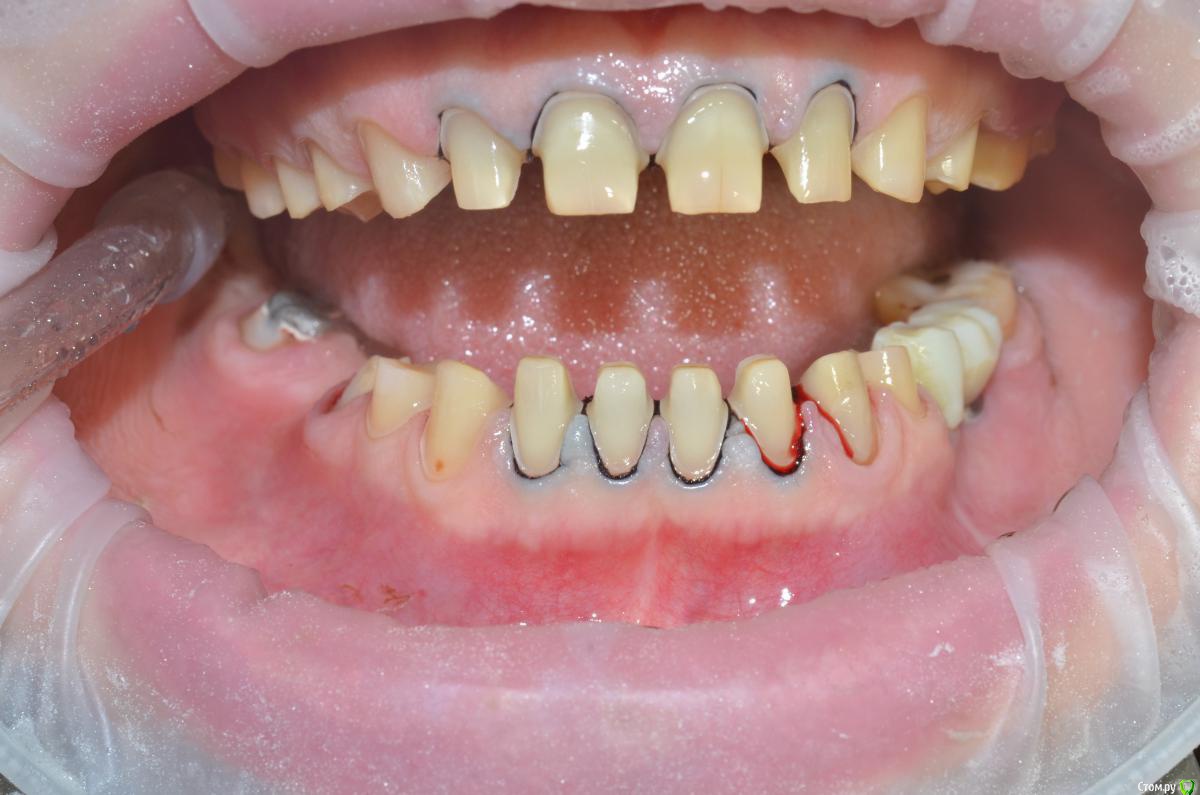

NazranDantist Опубликовано 21 мая, 2015 Поделиться Опубликовано 21 мая, 2015 (изменено) Коллеги поделитесь опытом. Какой план лечения предложить пациентке. Планируется тотальная работа что-нибудь из безметаловой технологии (E-max или претау, еще обдумываем). Вопрос, как выровнять оклюзионную плоскость, нужно ли прибегать к помощи ортодонта? Больше всего интересует первый сегмент, особенно зуб 15, висит слишком сильно. Или все таки стараться выйти из положения керамикой плюс хирургическое удлинение? Изменено 21 мая, 2015 пользователем NazranDantist Ссылка на комментарий

NazranDantist Опубликовано 4 сентября, 2015 Автор Поделиться Опубликовано 4 сентября, 2015 Продолжение кейса. Работа еще не закончена, зуб 25, 35, 36 - аббатменты на подходе, поэтому решили сделать после отпуска пациентки. Фото протокол не соблюдал, курс рубля прыгал, торопился в обменник . Вся работа - имакс на Цереке с редуцированием, фиксация - фронт на чойс, боковые - У-200. Ссылка на комментарий

CHEREDNICHENCO Опубликовано 13 сентября, 2015 Поделиться Опубликовано 13 сентября, 2015 Кариеса нет.DSC_0643.JPGСмещение естьПо фото, когда зубные ряды находятся в контакте- смещение есть! Но на первых фото, когда НЧ находиться в состоянии относительного физиологического покоя, смещения нет! ТО делаю вывод, смещение возникает в результате неправильного соотношения жевательных поверхностей зубов. Ссылка на комментарий